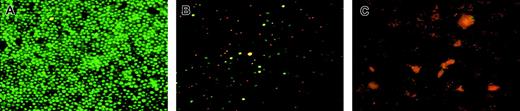

Figure 2C shows that, in order to survive, nonmigrated cells needed the addition of GM-CSF. All these results were confirmed by fluorescence microscopy (Figure 3), showing that most of migrated cells, cultured for 48 hours without GM-CSF, were stained with AO, but not with HO or PI (Figure 3A), indicating that they were alive, whereas more than 50% of nonmigrating cells were HO+ or PI+, indicating that they were apoptotic/dead cells (Figure 3B). Interestingly, cells that migrated across naked filters (in the absence of an endothelial monolayer; Figure 3C) are all necrotic, as indicated by AO+and PI+ staining. These data point to a high resistance of CD34+ cells to starvation and suggest that this population receives an antiapoptotic signal during transendothelial migration.

Viability of cells migrated through endothelium.

Peripheral blood CD14+ cells were allowed to migrate across HUVEC monolayers. (A) Migrated cells. (B) Nonmigrated cells. (C) Cells migrated through the naked filter without endothelium. Cells were submitted to triple staining with HO, AO, and PI and analyzed in fluorescence microscopy. Notice in panel A the prevalence of green living cells on red and yellow apoptotic cells. Nonmigrated cells (B) appear mostly as apoptotic-necrotizing cells (yellow nuclei) or late apoptotic–necrotizing cells (red nuclei). Conversely, only orange-stained cellular debris are detectable when cells passed through the naked filter (C). One representative experiment of 4 is shown; original magnification × 200 for all panels.